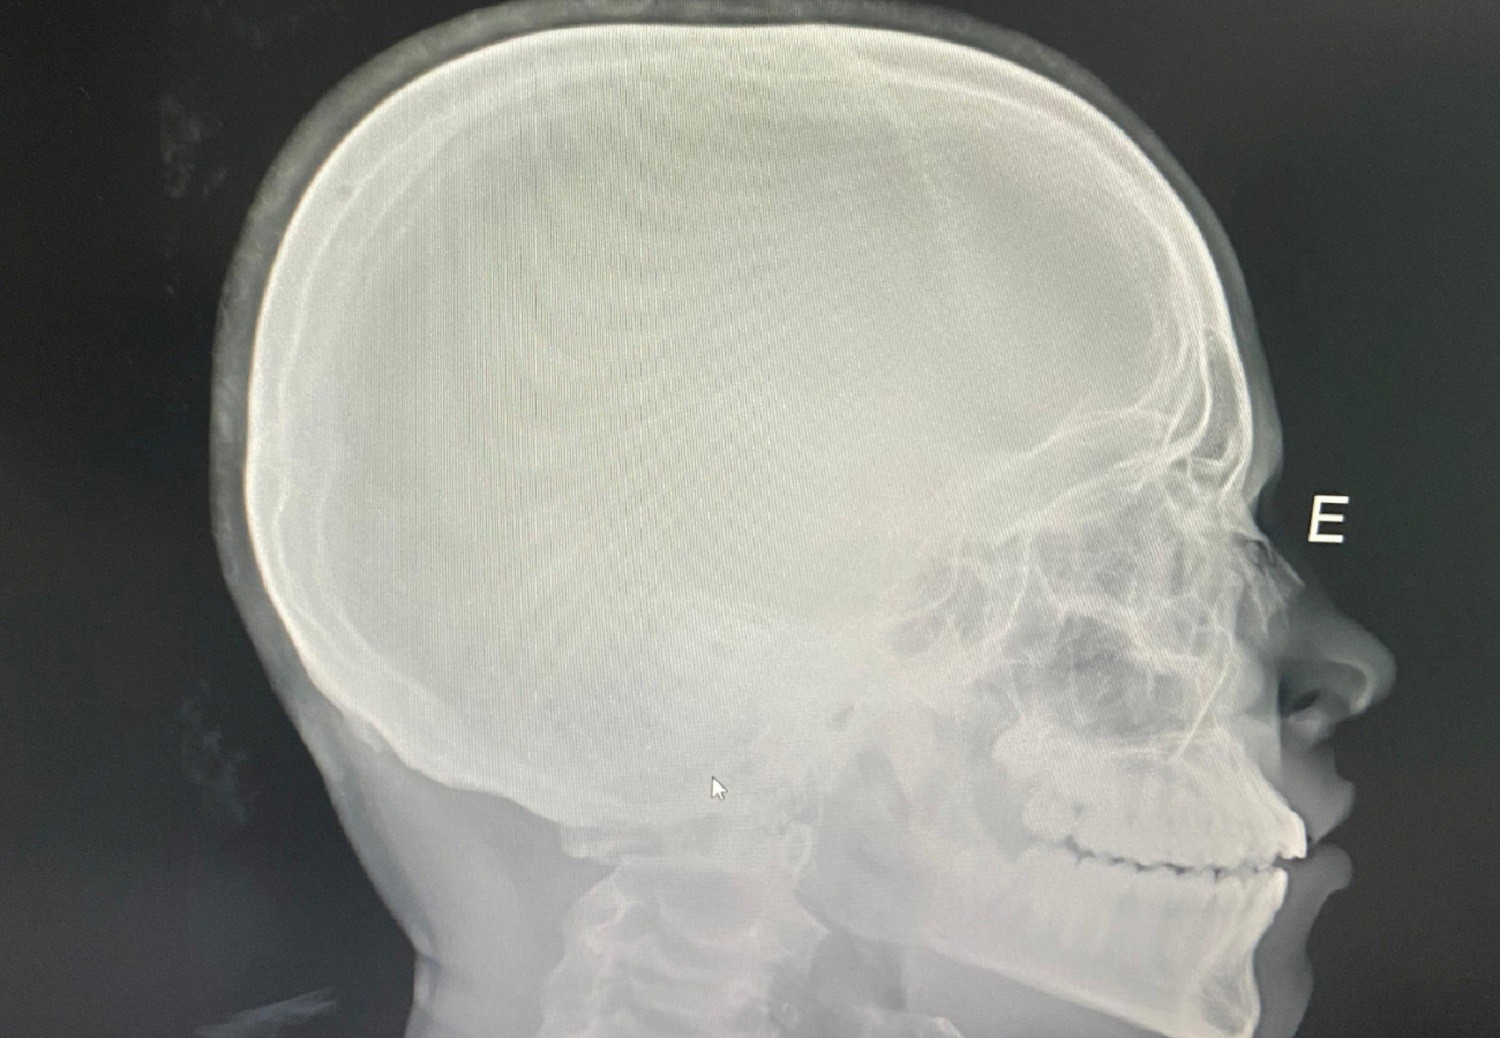

Estudante fraturou o nariz após ser agredido com um soco

Arquivo Pessoal/Vinicius Moraes